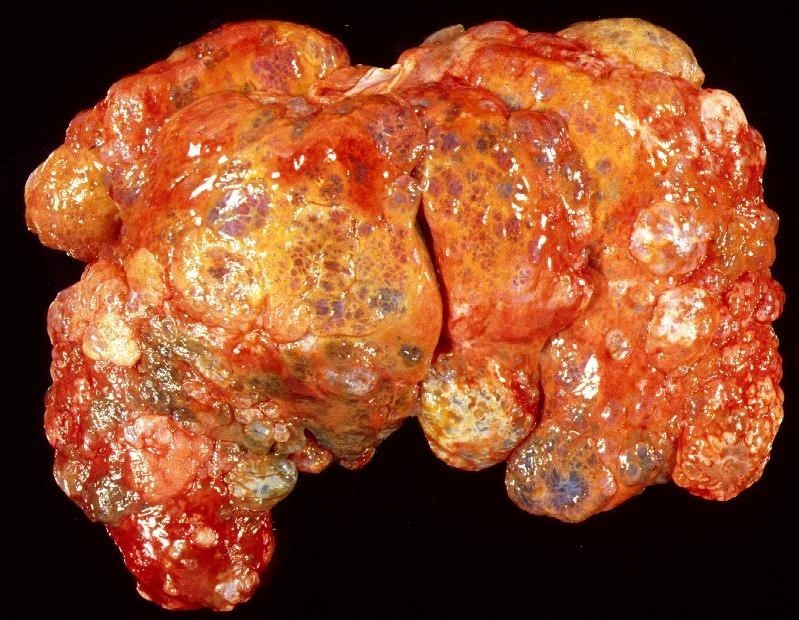

Describe this lesion

The entire liver parenchyma has been disrupted by disseminated fluid-filled, soft cystic structures. Areas of tissue which are not cystic show multifocal areas of haemorrhage or yellow discolouration.

Chronic disseminated severe polycystic hepatopathy

Genetic in persians